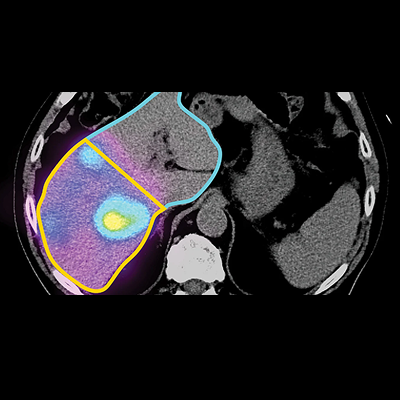

Post-Op Dosimetry

Calculate dose using Y90-PET and Bremsstrahlung SPECT. Calculate isodose curves/DVH on PET/SPECT using Local Disposition Method or

MIRD Kernal.